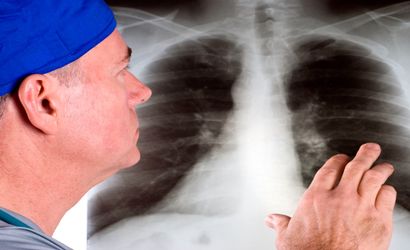

Akciğer kanserinde Türkiye şok edici bir rekor kırdı! Bu belirtiler sizi uyarıyor

Akciğer kanseri, dünyada en çok ölüme neden olan kanser türü. Türkiye'de ise durum daha da vahim. Uzmanlar, Türkiye'nin akciğer kanserinden ölüm hızı sıralamasında dünya ülkeleri arasında 4'üncü olduğunu açıkladı. Peki akciğer kanserinin belirtileri neler? Erken teşhis için ne yapmalı? İşte detaylar...

Türkiye, akciğer kanseri görülme sıklığı açısından erkeklerde dünya birincisi, her iki cinste ise 5'inci sırada yer alıyor. Bu hastalık, yılda yaklaşık 20 bin kişinin hayatını kaybetmesine neden oluyor. Akciğer kanserinin en büyük sebebi ise sigara. Uzmanlar, sigara içenlerin bu alışkanlıklarından bir an önce vazgeçmeleri gerektiğini vurguluyor. Peki akciğer kanserinin belirtileri neler, tedavisi var mı? Detaylarda...

Bu belirtilerden bir veya birkaçından yakınan kişilerin vakit kaybetmeden bir sağlık kuruluşuna başvurması gerekiyor ve en azından bir akciğer filmi çektirmesi gerekiyor.